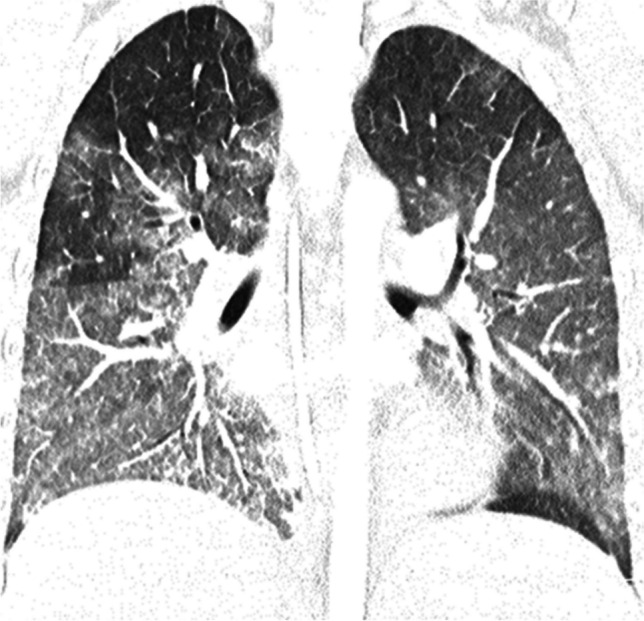

Chest radiography and CT can be helpful in reaching the diagnosis. Typical chest radiographic findings are pleural effusion, hilar lymphadenopathy, and patchy pulmonary consolidations with ground-glass opacities. On CT, ill-defined pulmonary nodules and consolidation with round low-attenuation cystic lesions filled with fluid or gas can be seen (Fig. 7); intra-cystic worms may be detected [60–62]. When children from endemic areas present with respiratory symptoms, laboratory findings of eosinophilia, and imaging demonstrations pleural effusion and lung consolidations with internal cystic lesions, diagnosis of paragonimiasis should be strongly considered.

Fig. 7.

Axial non-contrast-enhanced lung window computed tomography images in a 7-year-old girl with paragonimiasis who presented to hospital with abdominal pain and subcutaneous nodules. a Image at the level of the mid lung zone shows ill-defined lung nodules (white arrows) and a left-sided pleural effusion (black arrow). b Image at the level of the lower lung zone shows ill-defined lung nodules (thin arrow) and alveolar opacification (thick arrow) (figure from “A retrospective clinical analysis of pediatric paragonimiasis in a Chinese children’s hospital from 2011 to 2019” by Qian et al.; licensed under CC BY 4.0; original cropped and annotated)